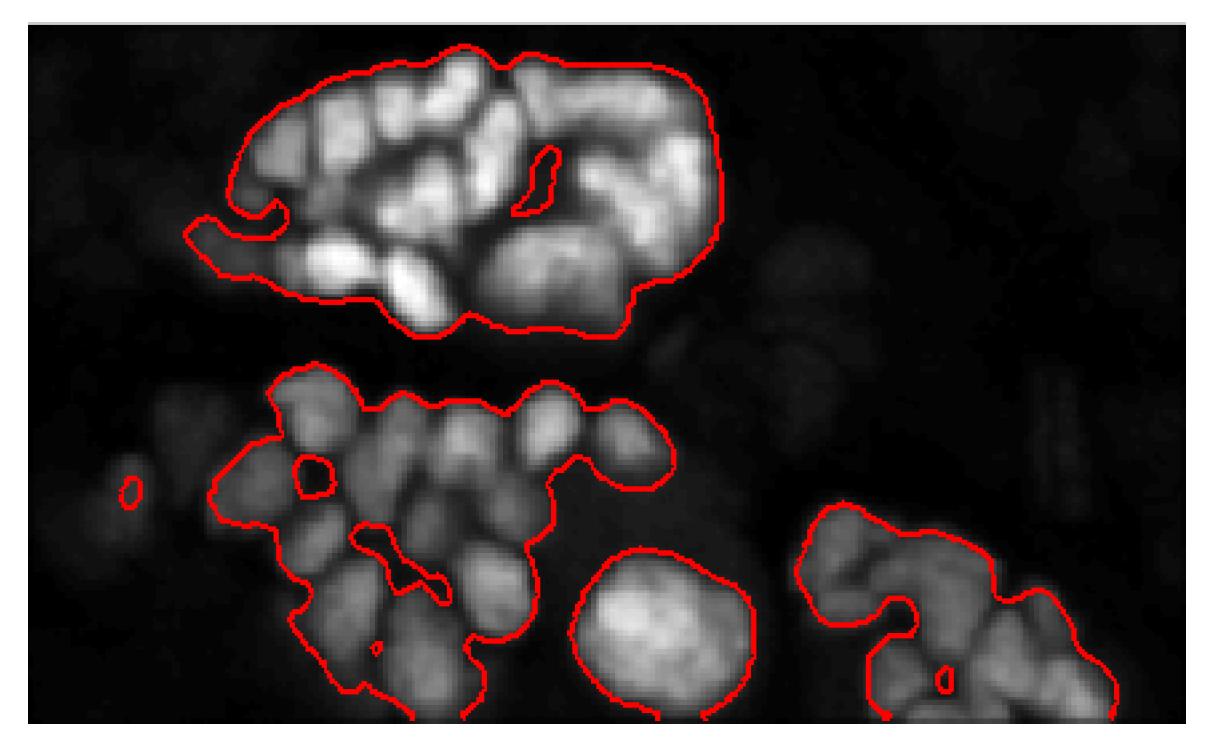

5.1. Evaluation on Sample Dataset